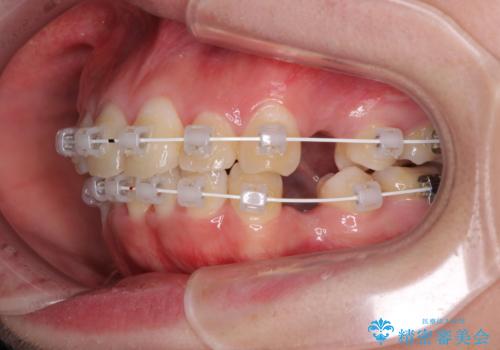

前歯の出っ歯と口の閉じにくさを抜歯矯正で改善 目立たないワイヤー矯正

- 上の前歯の出っ歯とでこぼこの歯並びを気にして来院された患者様です。

口元を積極的に引っ込めるために、上下左右の小臼歯4本を抜歯することとしました。

4本の歯を抜歯したことで、飛び出していた口元が引っ込み、横顔が大きく改善されました。

咬み合わせが悪化することのないようにスペースを閉じていくことができ、比較的スムーズに治療を進めることができました。